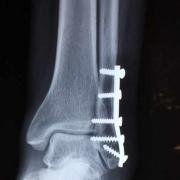

Open reduction and internal fixation of a fracture at the ankle.

In ORIF the surgeon cuts into the joint surgically to align the broken bones and then uses metal surgical plates or other means (loosely referred to as 'hardware') to hold the bones in a better position so that they can heal properly. Quick links

Devices are manufactured from metals and plastics that will withstand normal body forces, and resist breaking themselves, at least for long enough that the fracture can heal.

This may include wires as well as plates and screws. Removal is usually managed without problems, unless a lot of time has passed, when removal may prove problematic.